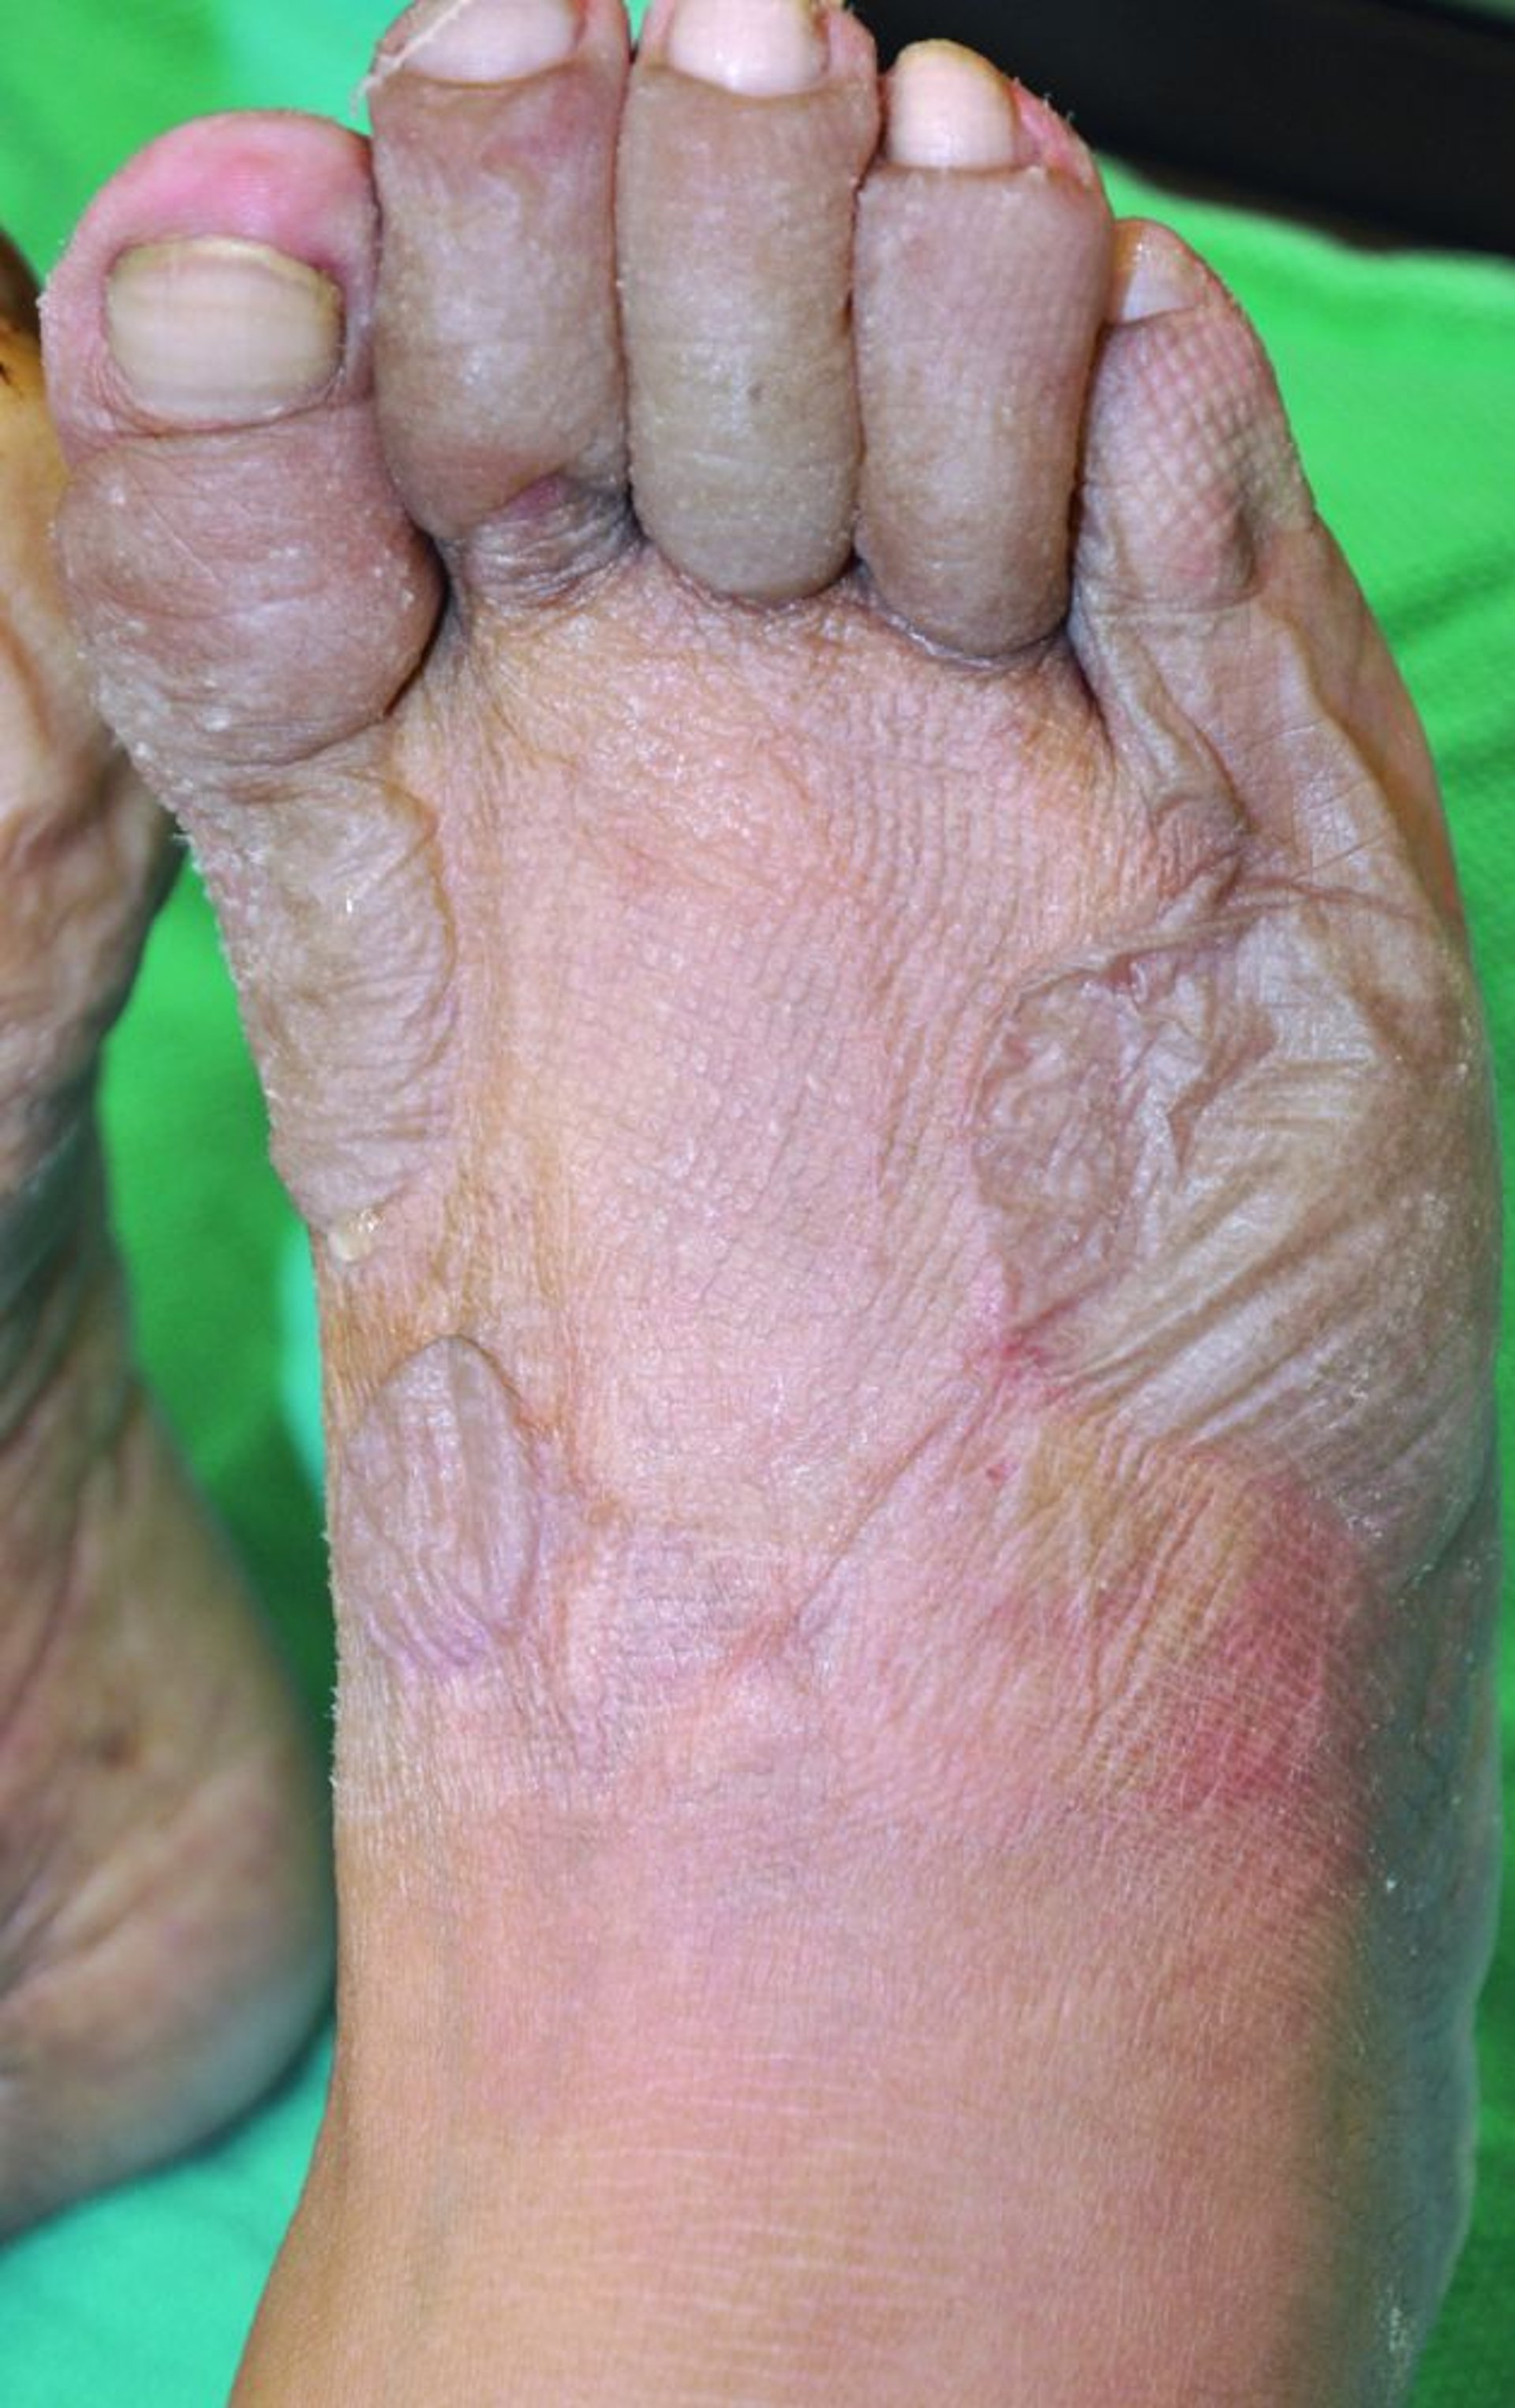

足の凍傷

この写真には,爪床が蒼白色になり,足趾が灰色に腫れ,水疱が生じた足が写っている。水疱内に血液がみられないことで,凍傷が表層的なものであり,治癒後に残存組織が失われる可能性が低いことが示されている。